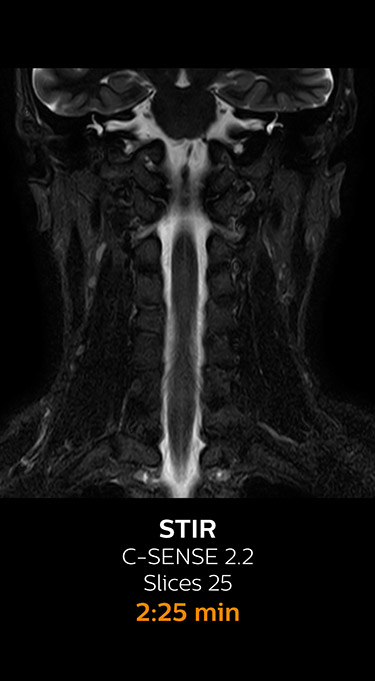

Fast MRI of cervical spine

With Compressed SENSE, the scan time for the routine cervical spine examination at KNC was reduced from 13:11 to 9:52 minutes, which corresponds to 25% reduction.

MRI examination of the cervical spine with Compressed SENSE

Ingenia 3.0T CX

Scan time 9:52 min. (was 13:11 min. without Compressed SENSE)